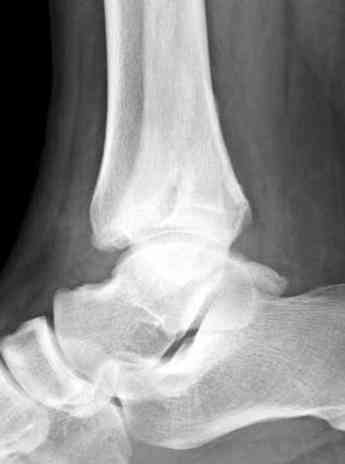

Здесь представлено решение похожей проблемы. Больной в течение года лечился консервативными мерами, и боли в голеностопе были основным показанием к операции.

Проведена обычная стандартная процедура по исправлению неудовлетворительного состояния голеностопного сустава, где кроме удлинения малоберцовой с применением compression tension device за проксимальный конец пластины, проведено замещение трикортикальным графтом из крыла, освобождение синдесмоза и медиальной щели от

фибротических масс с фиксацией.